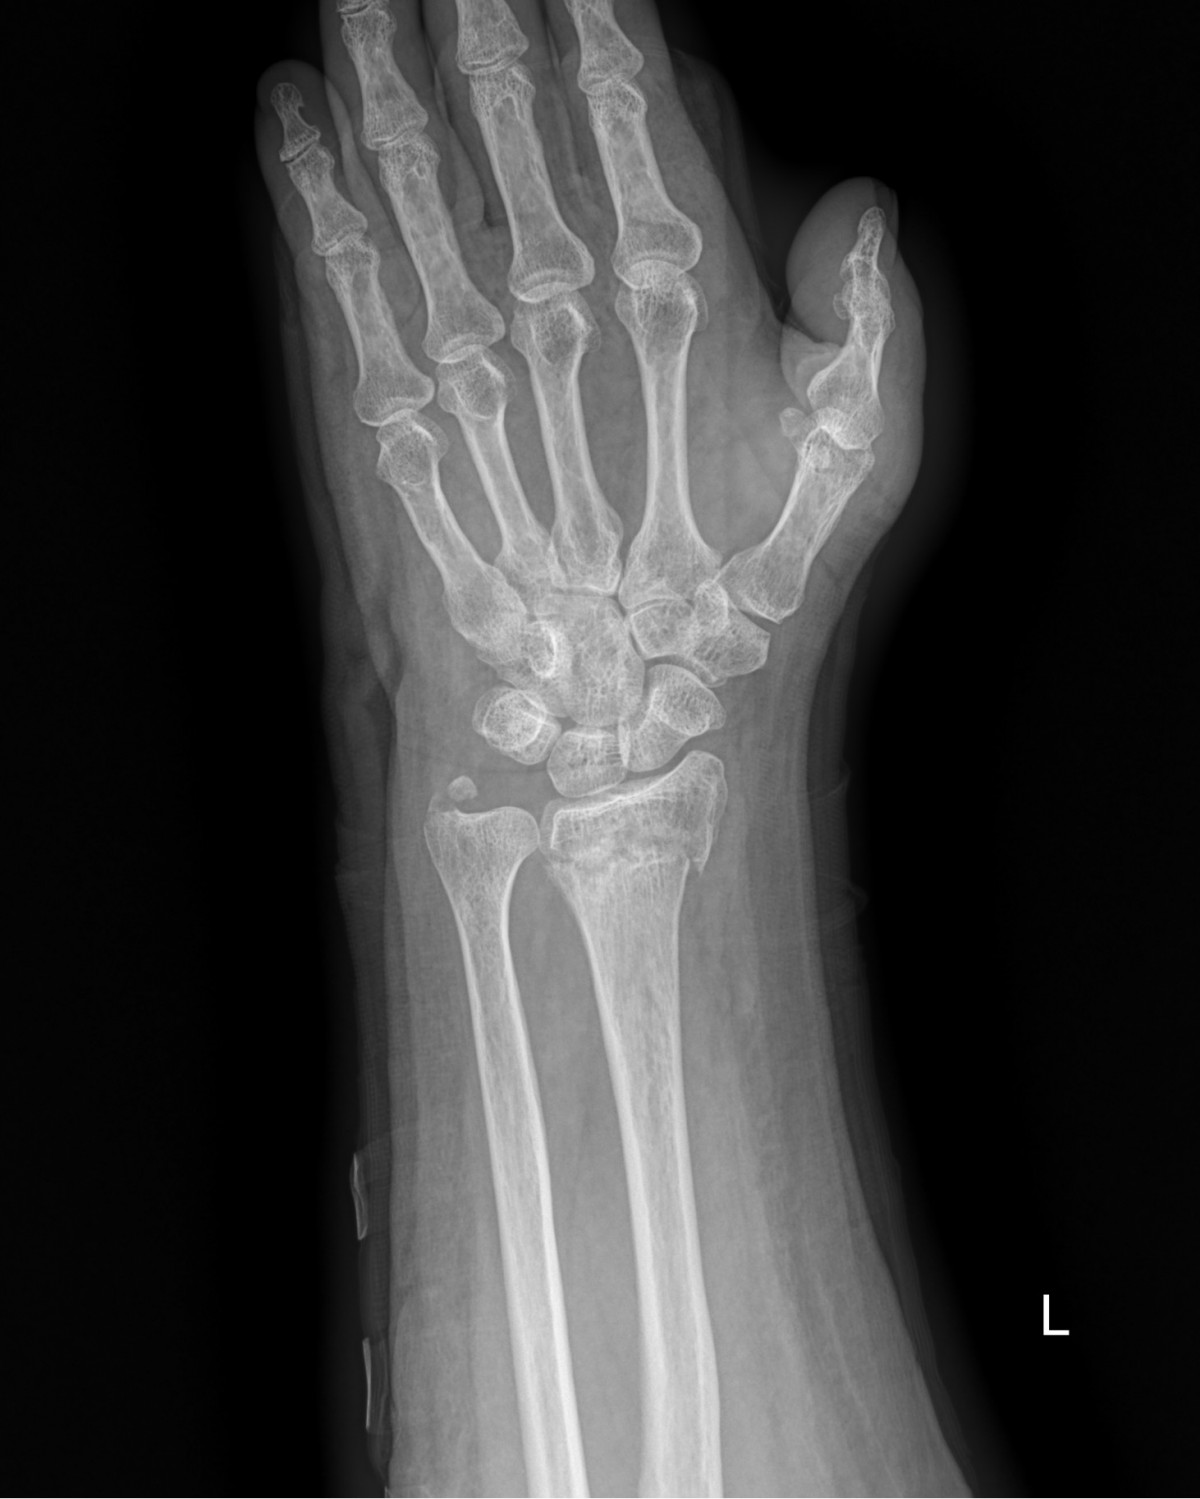

이재상원장님 손목 골절 수술 정명O 환자

dae765e4d9ac96aee867c9d6292d8784_1758002612_26.jpg